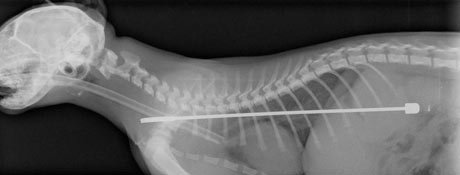

Σε έκτακτη χειρουργική επέμβαση υπεβλήθη νεαρός γάτος ονόματι Άλφι, η μανία του οποίου με την τηλεόραση τον έκανε να φάει την μήκους 15 εκατοστών κεραία της.

Αμετανόητος πολέμιος του απεχθούς μέσου μαζικής ενημέρωσης, το τετράποδο αιλουροειδές αποφάσισε να βάλει μια για πάντα τέλος στο «χαζοκούτι», ρίχοντάς το κάτω και «μασουλώντας» τη μεταλλική κεραία, η οποία ευτυχώς δεν του τραυμάτισε τη στομαχική κοιλότητα.